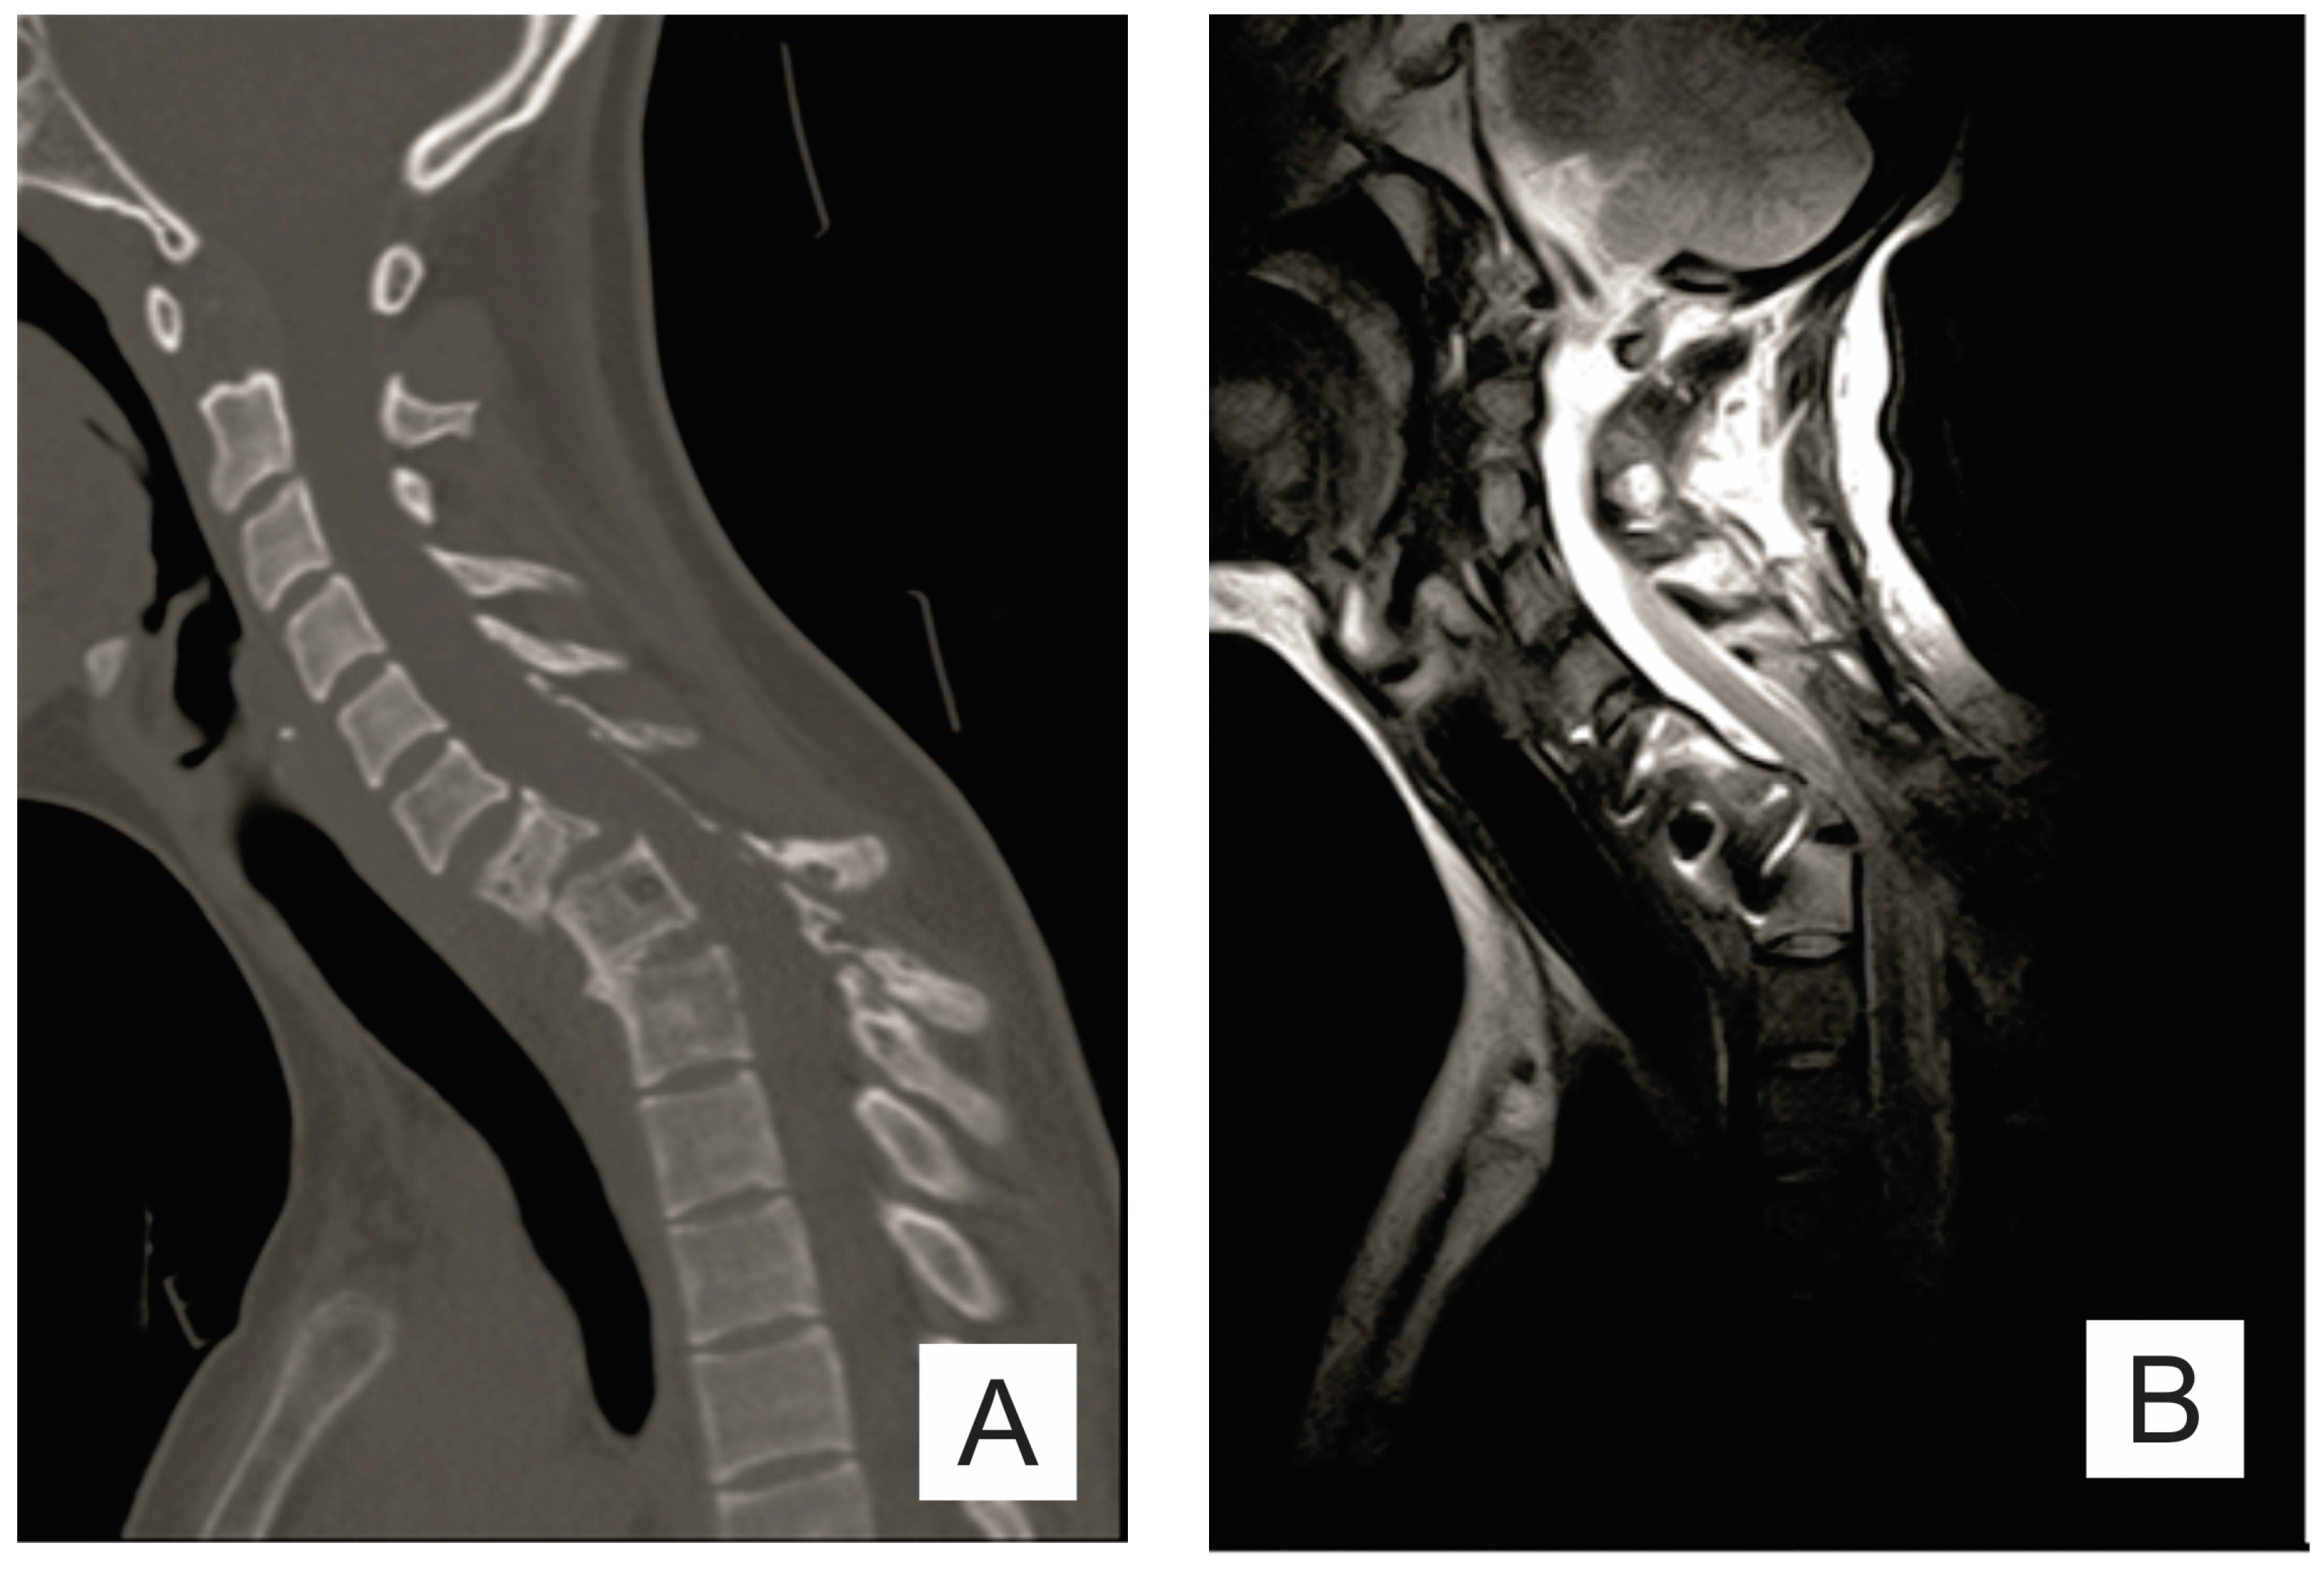

| Month I | C7 corpectomy and reconstruction with autologous graft from the iliac crest, macroscopic resection of the posterior arches C7-T1 and fixation with C4-C5-T3-T4 cervico-thoracic hybrid system |

| Month III | Ablation of osteosynthesis material and bone graft and T1 corpectomy, reconstruction with C6-T1 mesh fixed with proximal and distal screw |

| Month IX | Ablation of damaged osteosynthesis material mesh C6-T1, ablation of thoracic screws, and introduction of bilateral T3, T4, and T5 screws |